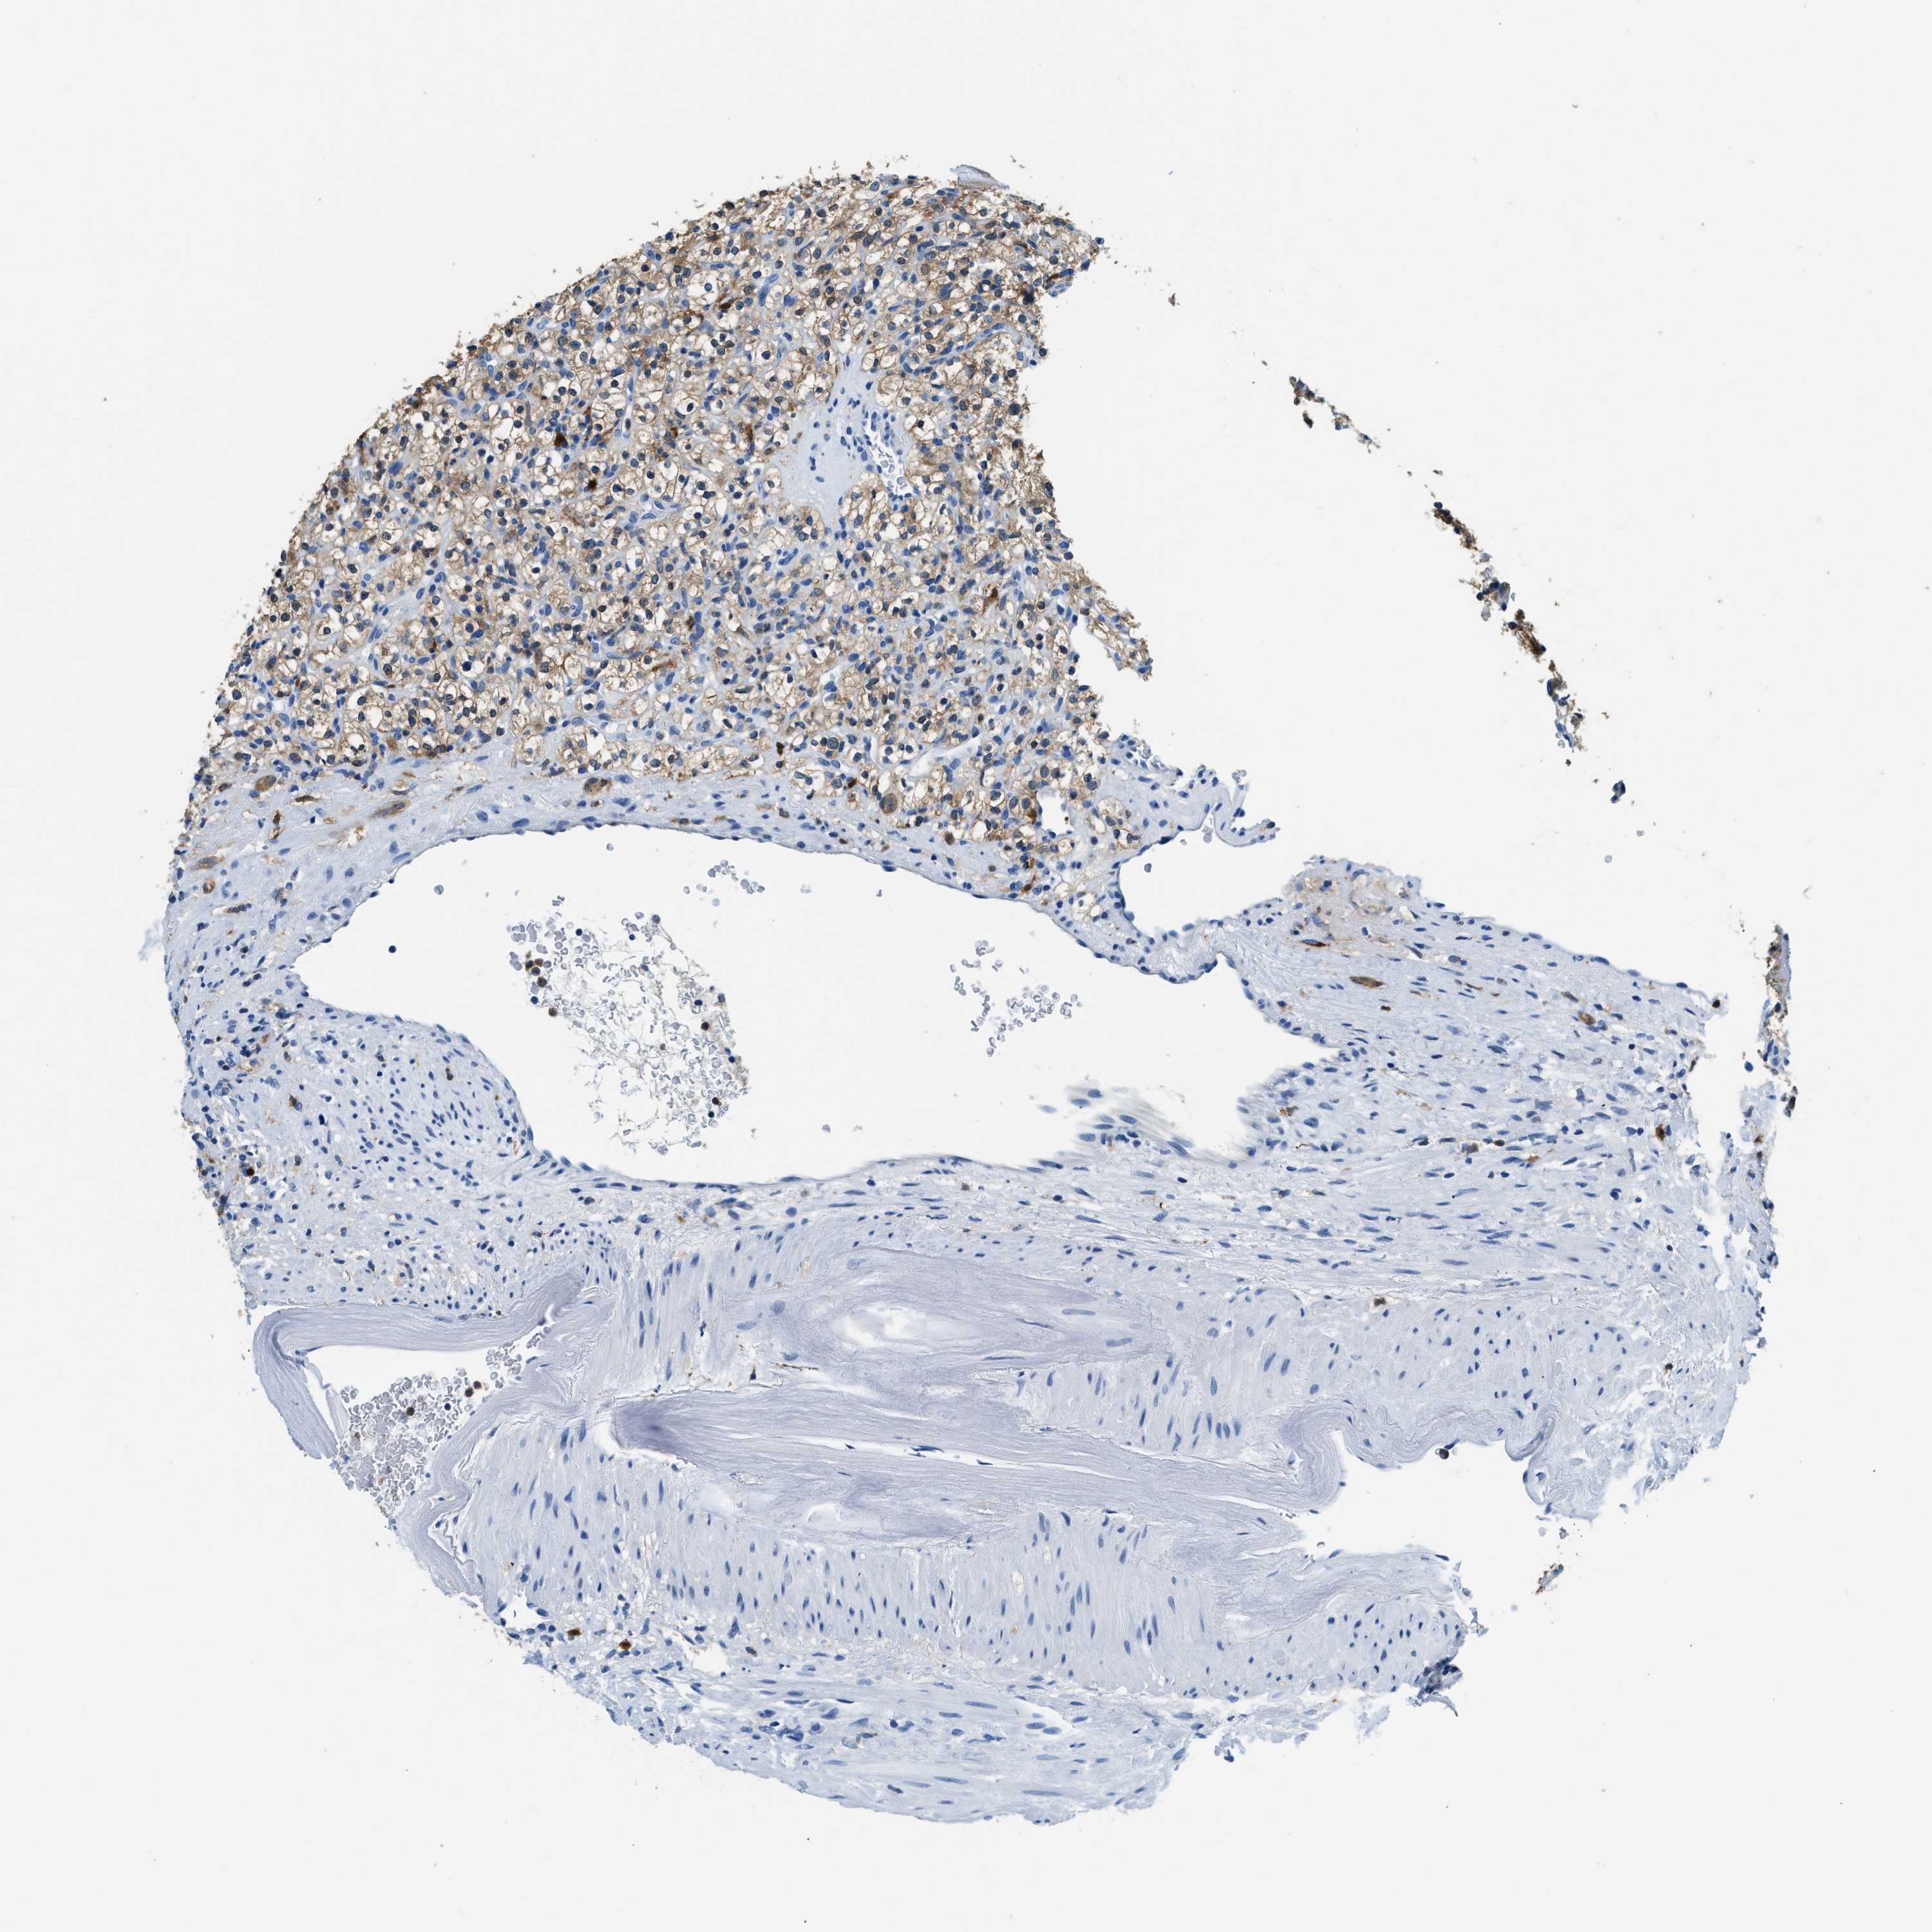

KIDNEY RENAL PAPILLARY CELL CARCINOMA (TCGA) - Interactive survival scatter ploti

The Survival Scatter plot shows the clinical status (i.e. dead or alive) for all individuals in the patient cohort, based on the same data that underlies the corresponding Kaplan-Meier plots. Patients that are alive at last time for follow-up are shown in blue and patients who have died during the study are shown in red.

The x-axis shows the expression levels (FPKM) of the investigated gene in the tumor tissue at the time of diagnosis. The y-axis shows the follow-up time after diagnosis (years). Both axes are complimented with kernel density curves demonstrating the data density over the axes. The top density plot shows the expression levels (FPKM) distribution among dead (red) and alive patients (blue). The right density plot shows the data density of the survived years of dead patients with high and low expression levels respectively, stratified using the cutoff indicated by the vertical dashed line through the Survival Scatter plot. This cutoff is automatically defined based on the FPKM cutoff that minimizes the p-score. The cutoff can be changed by dragging the vertical line or by entering a cutoff value in the square labeled "Current cut-off".

Under the Survival Scatter plot the p-score landscape (black curve; left axis) is shown together with dead median separation (red curve; right axis). Dead median separation is the difference in median mRNA expression between patients who have died with high and low expression, respectively. It is calculated as follows: median FPKM expression of dead patients with high expression - median FPKM expression of dead patients with low expression. This is intended to aid the user in visually exploring custom cutoffs and the associated p-scores and dead median separation.

Individual patient data is displayed and can be filtered by clicking on one or more of the category buttons on the top of the page. Categories describing expression level and patient information include: high, low, alive, dead, female, male and tumor stages. The scale of the x-axis can be toggled between linear and log-scale by clicking on the "x log" button. Mouse-over function shows TCGA ID, patient information and mRNA expression (FPKM) for each patient.

& Survival analysisi